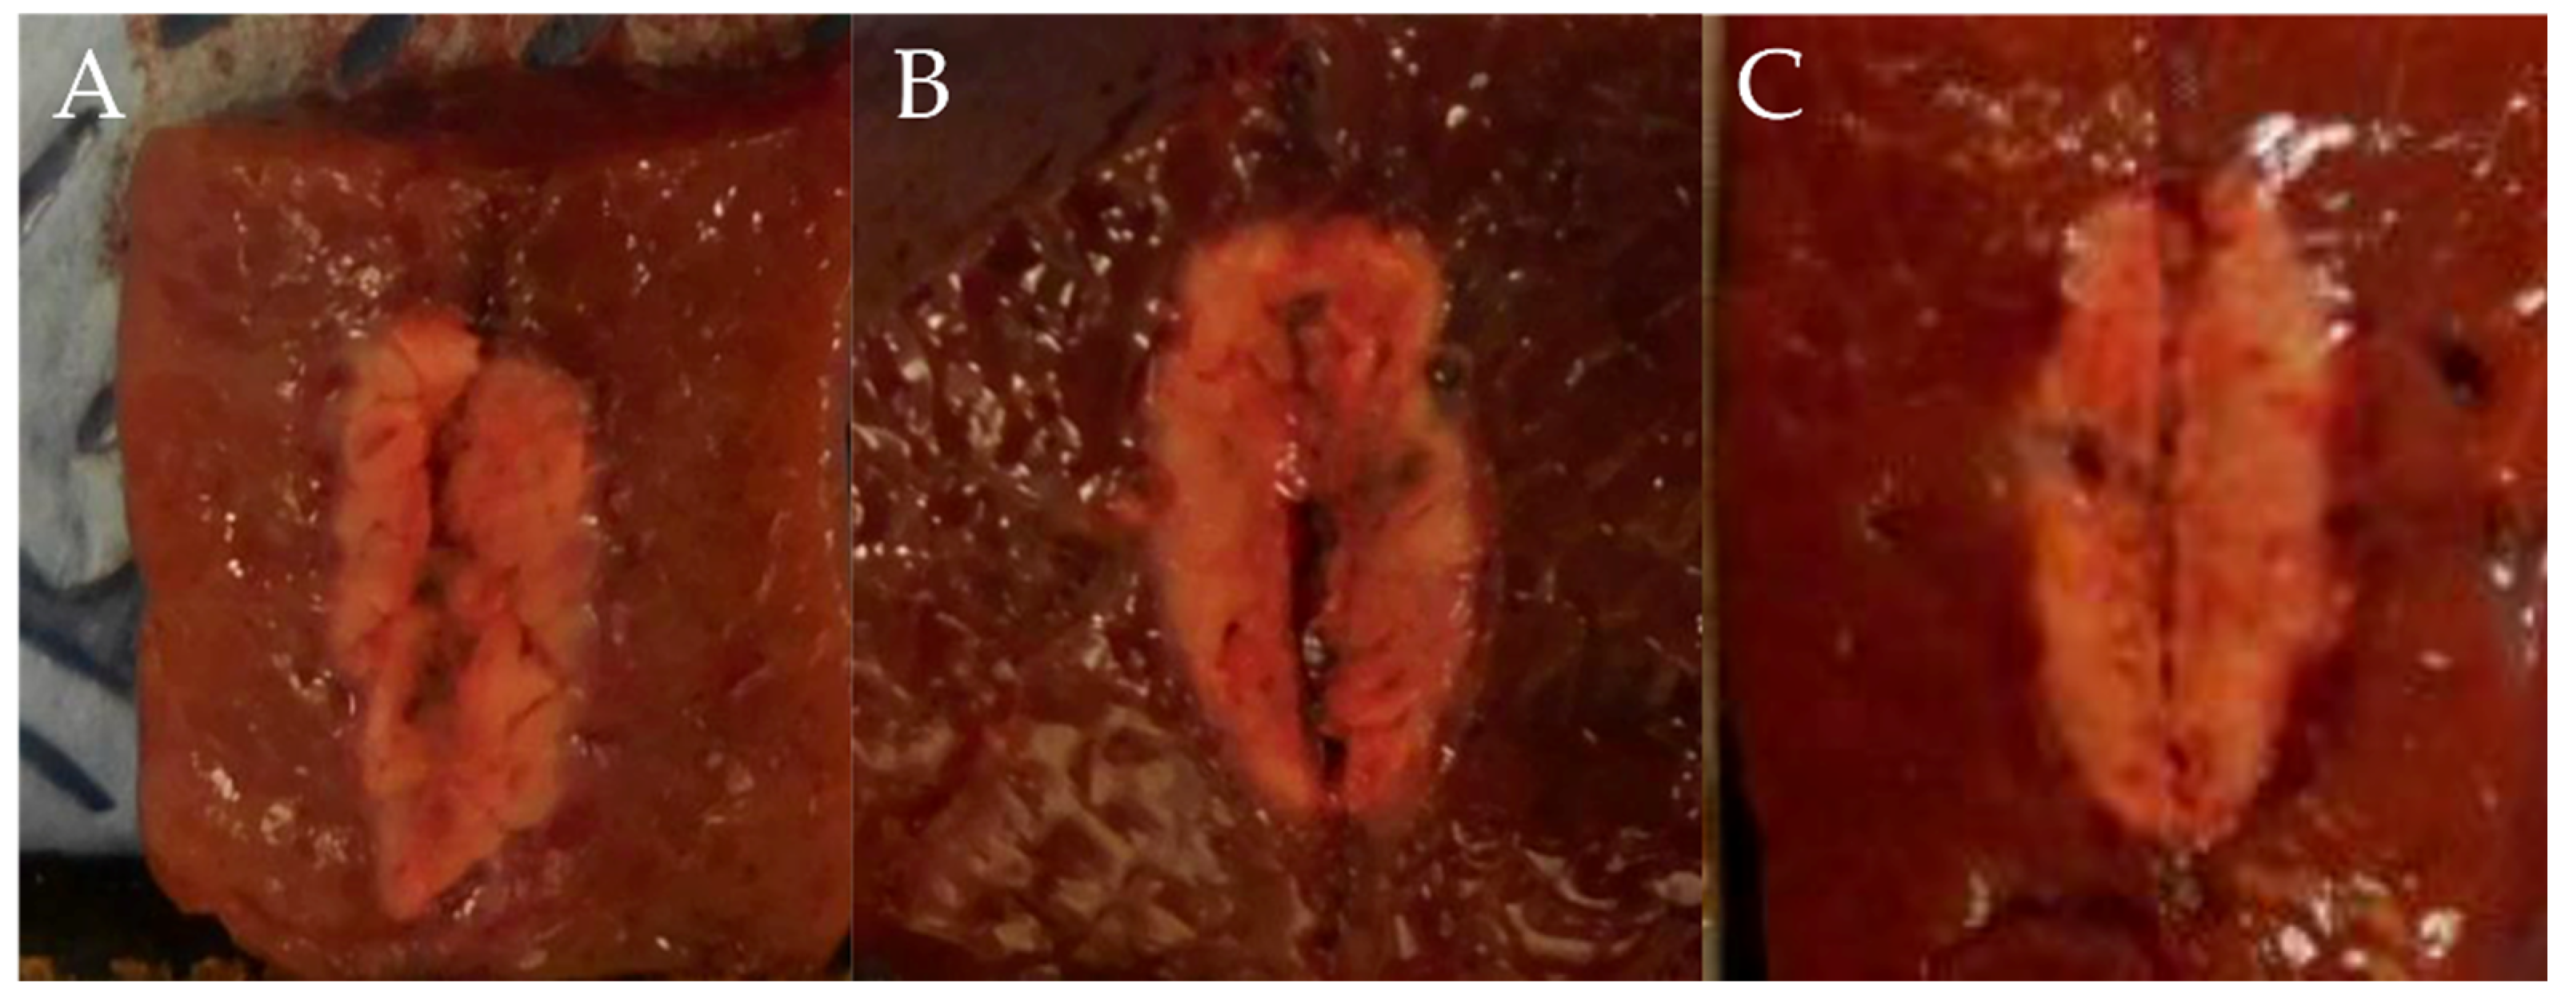

Gross necropsy findings showed a well-demarcated ablated lesion that could be distinguished from surrounding liver parenchyma by a whitish peripheral rim (Figure 2).

Figure 2.

Comparison of ablation zones based on electrode robe length and ablation power. (A) 0.5 cm, 10 W, 10 s. (B) 0.7 cm, 25 W, 10 s (C) 1 cm, 50 W, 10 s. (D) 1.5 cm, 75 W, 10 s. Specimens exhibit a well-demarcated ablated lesion that is distinguishable from the surrounding liver parenchyma.

In test one, at 0.5, 0.7, 1, and 1.5 cm probe tip lengths, the mean maximal injury widths were 0.46 ± 0.07, 0.54 ± 0.05, 0.65 ± 0.05, and 0.77 ± 0.02 cm, respectively, while the mean maximal injury depths were 0.65 ± 0.07, 0.92 ± 0.08, 1.26 ± 0.14, and 1.80 ± 0.11 cm, respectively (Table 1, Figure 2 and Figure 3). Therefore, injury width and depth increased with electrode length and RFA power. The roll-off phenomenon occurred between 7 s and 8 s in each procedure.

In test two, in groups A (1 cm, 30 W, 10 s), B (1 cm, 30 W, 15 s), and C (1 cm, 50 W, 10 s), the mean maximal injury widths were 0.56 ± 0.05, 0.65 ± 0.06, and 0.65 ± 0.05 cm, respectively, while the mean maximal injury depths were 1.06 ± 0.29, 1.14 ± 0.05, and 1.26 ± 0.09 cm, respectively (Table 2, Figure 4 and Figure 5). Therefore, the maximal injury width and depth were similar between groups B and C (Table 2). The roll-off phenomenon occurred between 12 and 15 s in group B.